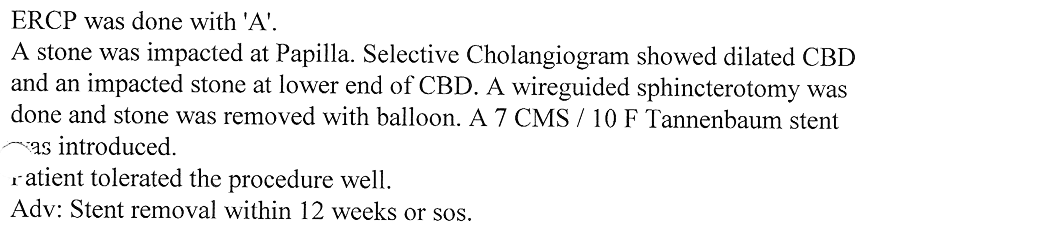

Endoscopic Retrograde Cholangio Pancreatography is an advanced endoscopic procedure related to

diseases of pancreas and biliary tree. Common indication for ERCP is jaundice due to obstruction

of biliary tube, which drains the bile from the liver into the intestine.

Obstruction can be due to a gallstone, which has slipped into bile tube and has blocked the bile tube.

These Stones can be removed by ERCP, without any surgery being involved.

Common Biles Duct Stones

Common Biles Duct Stones

Impacted Stone in Common Bile Duct